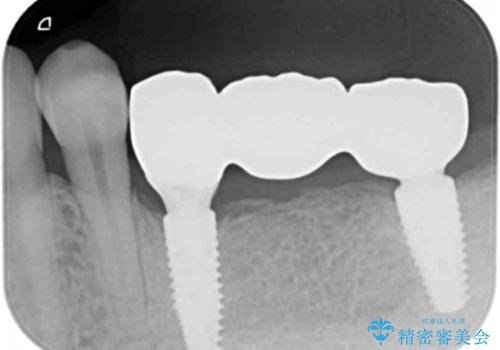

- 89.1万円(仮歯×3・ストローマンインプラント×3・フルジルコニアクラウン×3・チタンカスタムアバットメント×3)費用は治療当時の料金となります

インプラントは複数の奥歯を失った際に、咬合機能をしっかりと回復できる有効な治療です。

治療後はまたしっかりと噛んで食事を楽しむことができるようになったと喜んでいただくことができました。